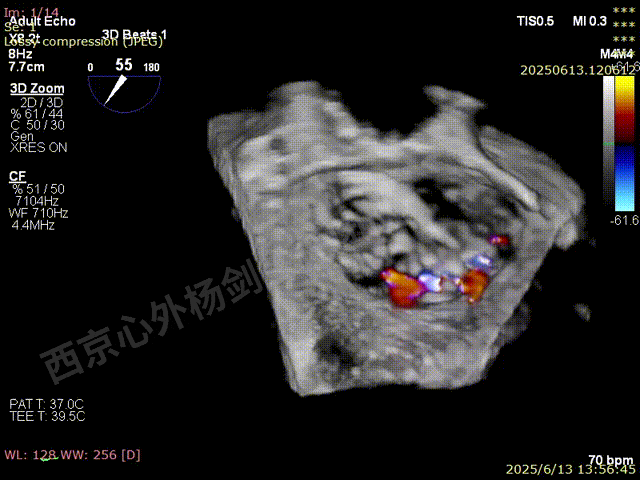

夹子关闭后检查夹子两侧反流

第一枚XTW释放后评估,外侧反流基本消失,内侧仍然有中度以上反流

第二枚XT于第一枚夹子内侧瓣上调整

第二枚XT关闭后评估,trace

二尖瓣平均跨瓣压差1mmHg

释放后评估,反流降至1+,组织桥稳定

M-TEER术后三尖瓣反流减轻